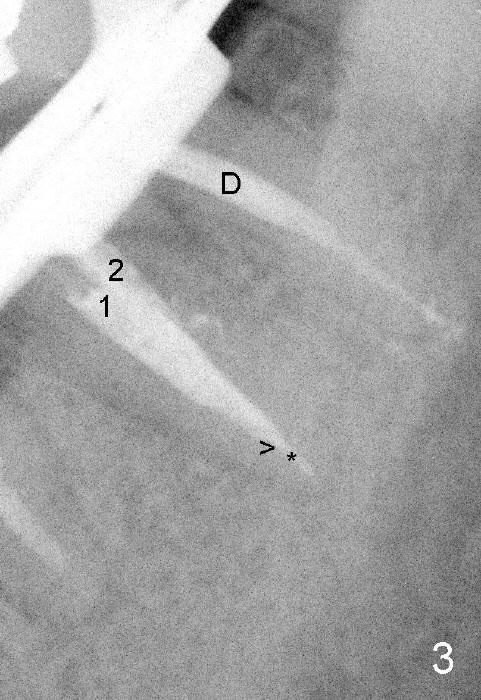

插入主牙胶尖(近中颊侧30/.04,近中舌侧30/.06,远中40/.04)后,拍摄根尖片(图二),近中牙胶尖(1,2)部分与断针(*)重叠,箭头指向牙胶尖下端,D是远中牙胶尖。然后准备根管充填,用纸尖吸干根管时,断针看得很清楚,接着使用Piezo超声波加上diamond tip在扩大断针周围扩大根管,用hand files能拨动断针,但是不能让断针上下移动,虽然我们有微型钳子,但是估计头还是太大,插不进根管里。最后还是草率收兵:根管充填,近中颊侧,远中根管使用主牙胶尖外,还插入多根副牙胶尖,而近中舌侧根管就使用一个主牙胶尖(图三):*:断针,箭头:充填下端。最后做树脂buildup,现在术后一个多月,病人好像没事,不想近期回诊所做下一步治疗。